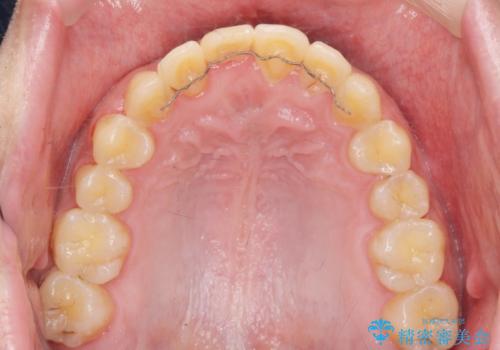

- ワイヤー矯正 → インビザライン

- 3年

見た目、噛み合わせが大きく改善し、大変喜んでいただくことができました。